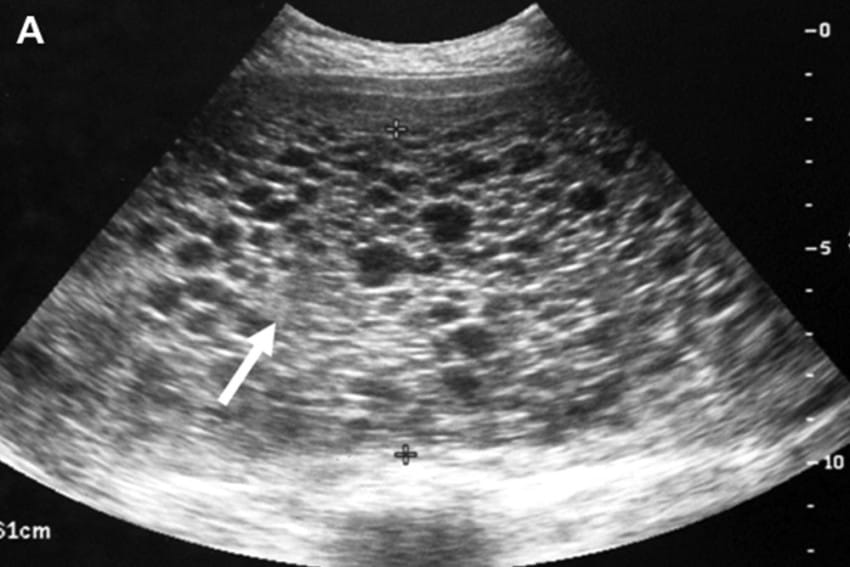

Η σύζυγός μου ήταν πολύ άρρωστη στο μεγαλύτερο μέρος της εγκυμοσύνης, η οποία δεν έμοιαζε την πρώτη σε τίποτα. Στις 11 εβδομάδες, είχαμε το πρώτο μας υπερηχογράφημα και η είδηση δεν ήταν καθόλου καλή.

photo credit:imgur

Δεν υπήρχε μωρό. Αντ ‘αυτού, αυτό που βλέπαμε έμοιαζε με ένα τσαμπί σταφύλια. Ήταν ένας όγκος.

Αυτό το αποκαλούν ως μύλη κύηση. Η σύζυγός μου έπρεπε να χειρουργηθεί αμέσως. Επειδή η μύλη κύηση είναι αγγειακή, ο χειρουργός έπρεπε να προετοιμαστεί για μια πλήρη υστερεκτομή.